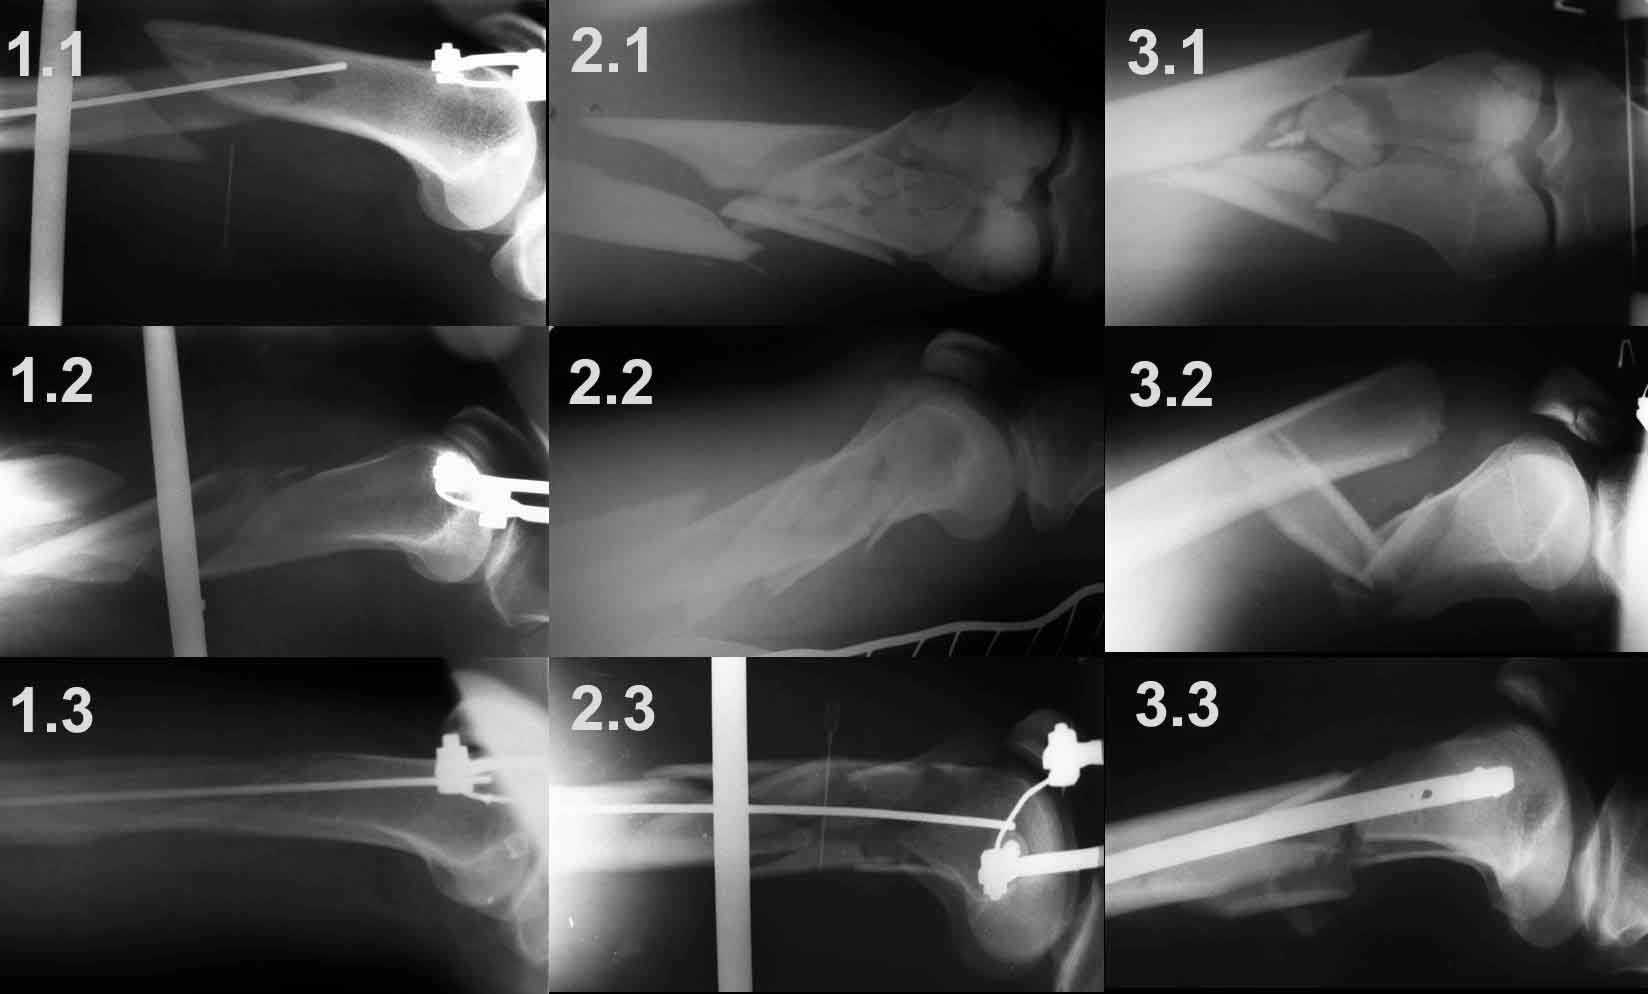

Для примера – вложенный файл.

1.1 – спица проведена сразу за передним кортикальным слоем дистального отломка, поэтому при дистракции появляется задний угол.

1.2 - спица проведена на линии середины диафиза бедренной кости, что привело к передней угловой деформации

1.3 - спица проведена в механически обоснованной точке (0,5 – 0,7 см дорсальнее передней поверхности кортикального слоя), что привело к репозиции костных отломков и ликвидации угловых деформаций.

2.1 -2.3 и 3.1 – 3.3 служат подтверждением того, что любую угловую деформацию при коротком дистальном отломке можно весьма просто устранить, правильно расположив спицу цуг-аппрата.